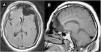

Treatment for brain arteriovenous malformations (AVM) include combinations of surgery, radiosurgery and embolization. Very rarely, spontaneous obliteration may occur, especially among small lesions with single superficial vein drainage and prior bleeding. We report the case of a large symptomatic AVM, without history of hemorrhage or prior treatment, in which self-obliteration was noted at surgery. Although MRI suggested the presence of an AVM, no evidence of arterial anomaly was observed in the brain angiography. At surgery, a large cortical nidus with tortuous arterial vessels, resembling that of an AVM but without blood flow, was identified. Complete resection was easily performed without relevant bleeding. The histopathologic study confirmed the diagnosis of a thrombosed AVM. Despite the low probability of recanalization, surgical resection of a suspected spontaneously obliterated AVM may be warranted, in order to reach a definitive diagnosis and to avoid the risk of an eventual bleeding, especially among younger patients.